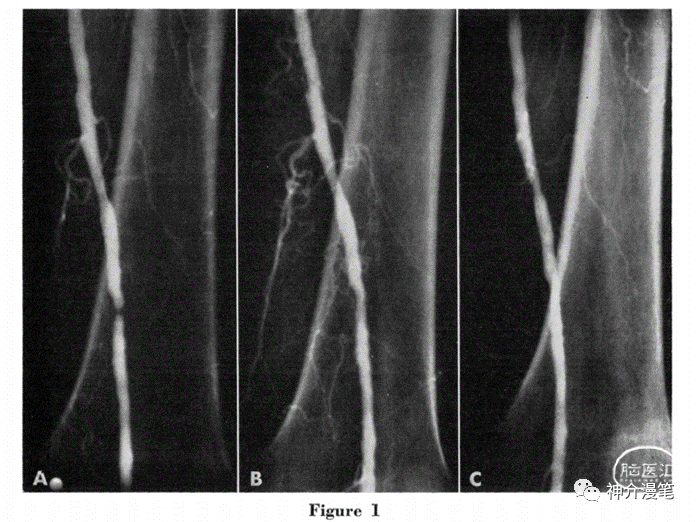

1974年,Gruntzig and Hopf首次报道使用非顺应性球囊扩张下肢动脉狭窄,使得介入治疗真正的进入了一个新的纪元。1977年,Gruntzig 首次报道使用球囊进行冠脉扩张成型术,从此冠脉介入的春天真实的到来了。